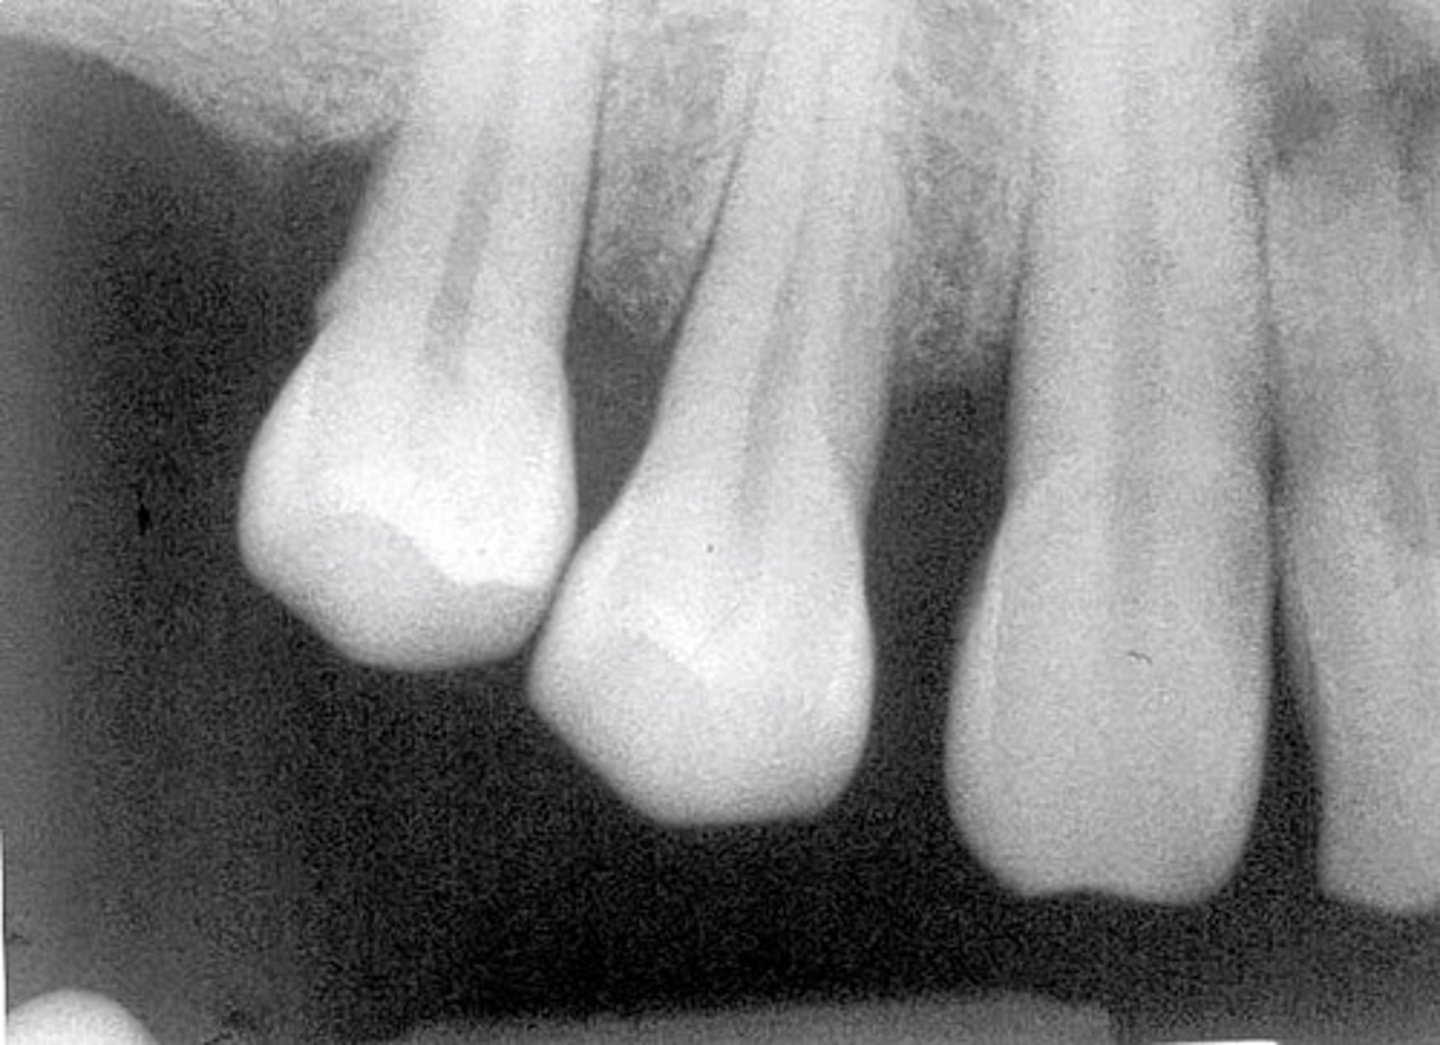

Apical cut-off